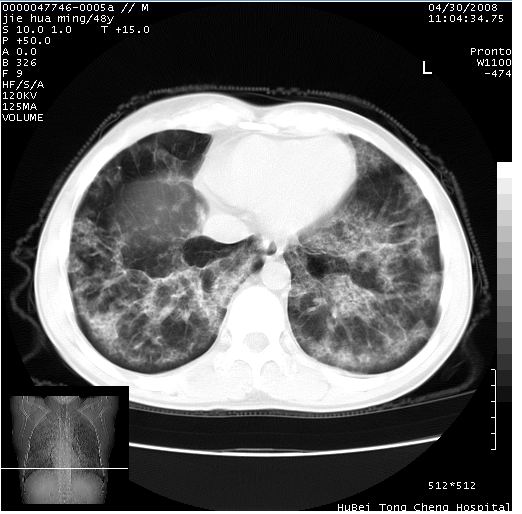

以下是引用dr.yang在2008-5-1 6:25:00的发言:[br]两肺广泛毛玻璃样的片状影,密度不均,边缘欠清,呈碎石路样改变,[br]考虑,1双肺间质性肺炎,2肺泡蛋白沉积症3支气管肺泡癌[br]

以下是引用hhcckk在2008-5-1 8:06:00的发言:[br]支持肺泡蛋白沉积症[br]依据:[br]1、病灶边缘清楚----地图征[br]2、病灶内部小叶间隔或小叶内间隔增厚所形成的网格状影----碎石路样表现[br]3、抗炎治疗无效(炎症抗炎治疗有效)[br]4、纵隔内未见肿大淋巴结(肺泡细胞癌时常有)[br][br]附肺泡蛋白沉积症资料[br][br]肺泡蛋白沉积症(pulmonary alveolar proteinosis)是一种原因不明的以肺泡腔内大量含脂糖蛋白样物质沉积为特征的疾病。[br]病理改变:(1)肺泡和细支气管腔内充满大量含脂糖蛋白样的粘稠物质,该物质为颗粒状或絮状的糖原pas染色阳性的磷脂蛋白。(2)肺泡壁及其间隔无异常改变。胸膜和淋巴结不受累及。(3)晚期可出现弥漫性肺间质纤维化。[br]临床表现:(1)好发年龄30~50岁,男性多于女性,偶见于儿童;(2)主要症状为呼吸困难、咳嗽、低热、消瘦、低氧血症和杵状指等。1/3的患者无症状。(3)实验室检查:痰液或肺泡灌洗液中可找到pas染色阳性颗粒物质。[br]hrct表现:肺泡蛋白沉积症具有特征性改变,即“碎石路样”表现(crazy-paving appearance,cpa)。主要包括(1)斑片状磨玻璃影:指肺野密度朦胧增加,内可见肺血管纹理影,系肺泡腔内充满低密度的磷脂蛋白物质所致。(2)其内部小叶间隔或小叶内间隔增厚所形成的网格状影,为小叶间隔水肿、肺泡壁内淋巴细胞和巨噬细胞浸润以及小叶内淋巴管扩张的缘故。(3)病灶边缘清楚,呈地图样分布于肺野外围或肺门及中央区。[br]

以下是引用zsl6918在2008-5-1 7:35:00的发言:[br]双肺磨玻璃样病变,可见铺碎路石征,病变区与正常区交错。边界清晰。符合肺泡蛋白质沉着征,高分辨扫描会更清楚漂亮。建议临床肺泡灌洗。

以下是引用yangyudong333在2008-5-1 5:36:00的发言:[br][br] 两肺广泛毛玻璃样的片状影,密度不均,边缘欠清,呈碎石路样改变,[br]考虑,1双肺间质性肺炎,2肺泡蛋白沉积症[br]